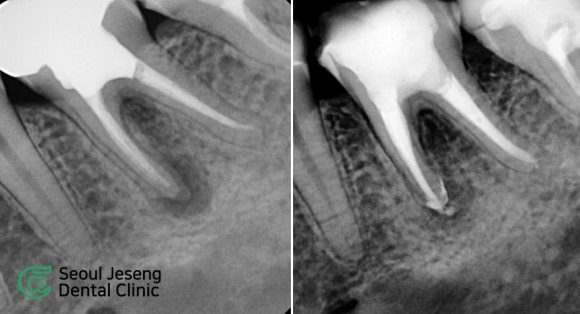

[치료사례] 재신경치료 (5)

Seoul Jeseng Dental Korea - English, French Speaking Dentist | 서울재생치과 - 임플란트 투명교정 신경치료의 네이버 블로그 원문을 보존한 아카이브 페이지입니다. 치료사례/생생후기 카테고리의 [치료사례] 재신경치료 (5) 글을 통해 병원의 한국어 정보 제공 방식과 진료 관련 안내 톤을 확인할 수 있습니다.